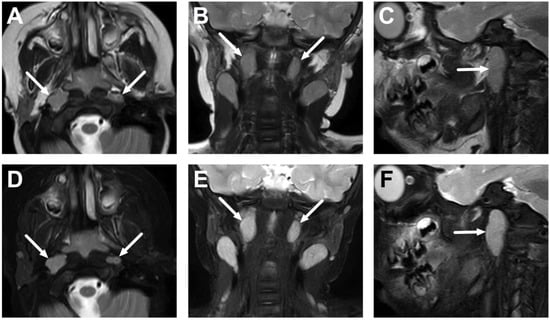

4.1. Tonsillitis, Peritonsillar Abscesses, and Parapharyngeal Abscesses

4.2. Retropharyngeal Abscesses and Suppurative Lymphadenitis